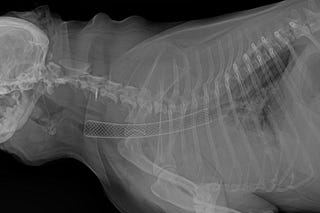

Colocación de un stent traqueal en un perro con colapso traqueal

Abordamos paso a paso la colocación de este dispositivo en un perro con colapso traqueal severo